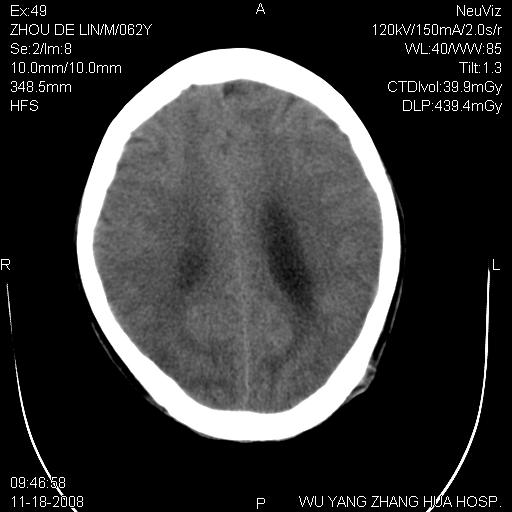

患者近段时间偶有头晕,无其他不适。既往有糖尿病病史。

小脑囊实性占位病变、脑室系统积水扩张、脑肿胀。

小脑囊实性占位病变、脑室系统积水扩张,建议增强

小脑囊实性占位病变、脑室系统积水扩张